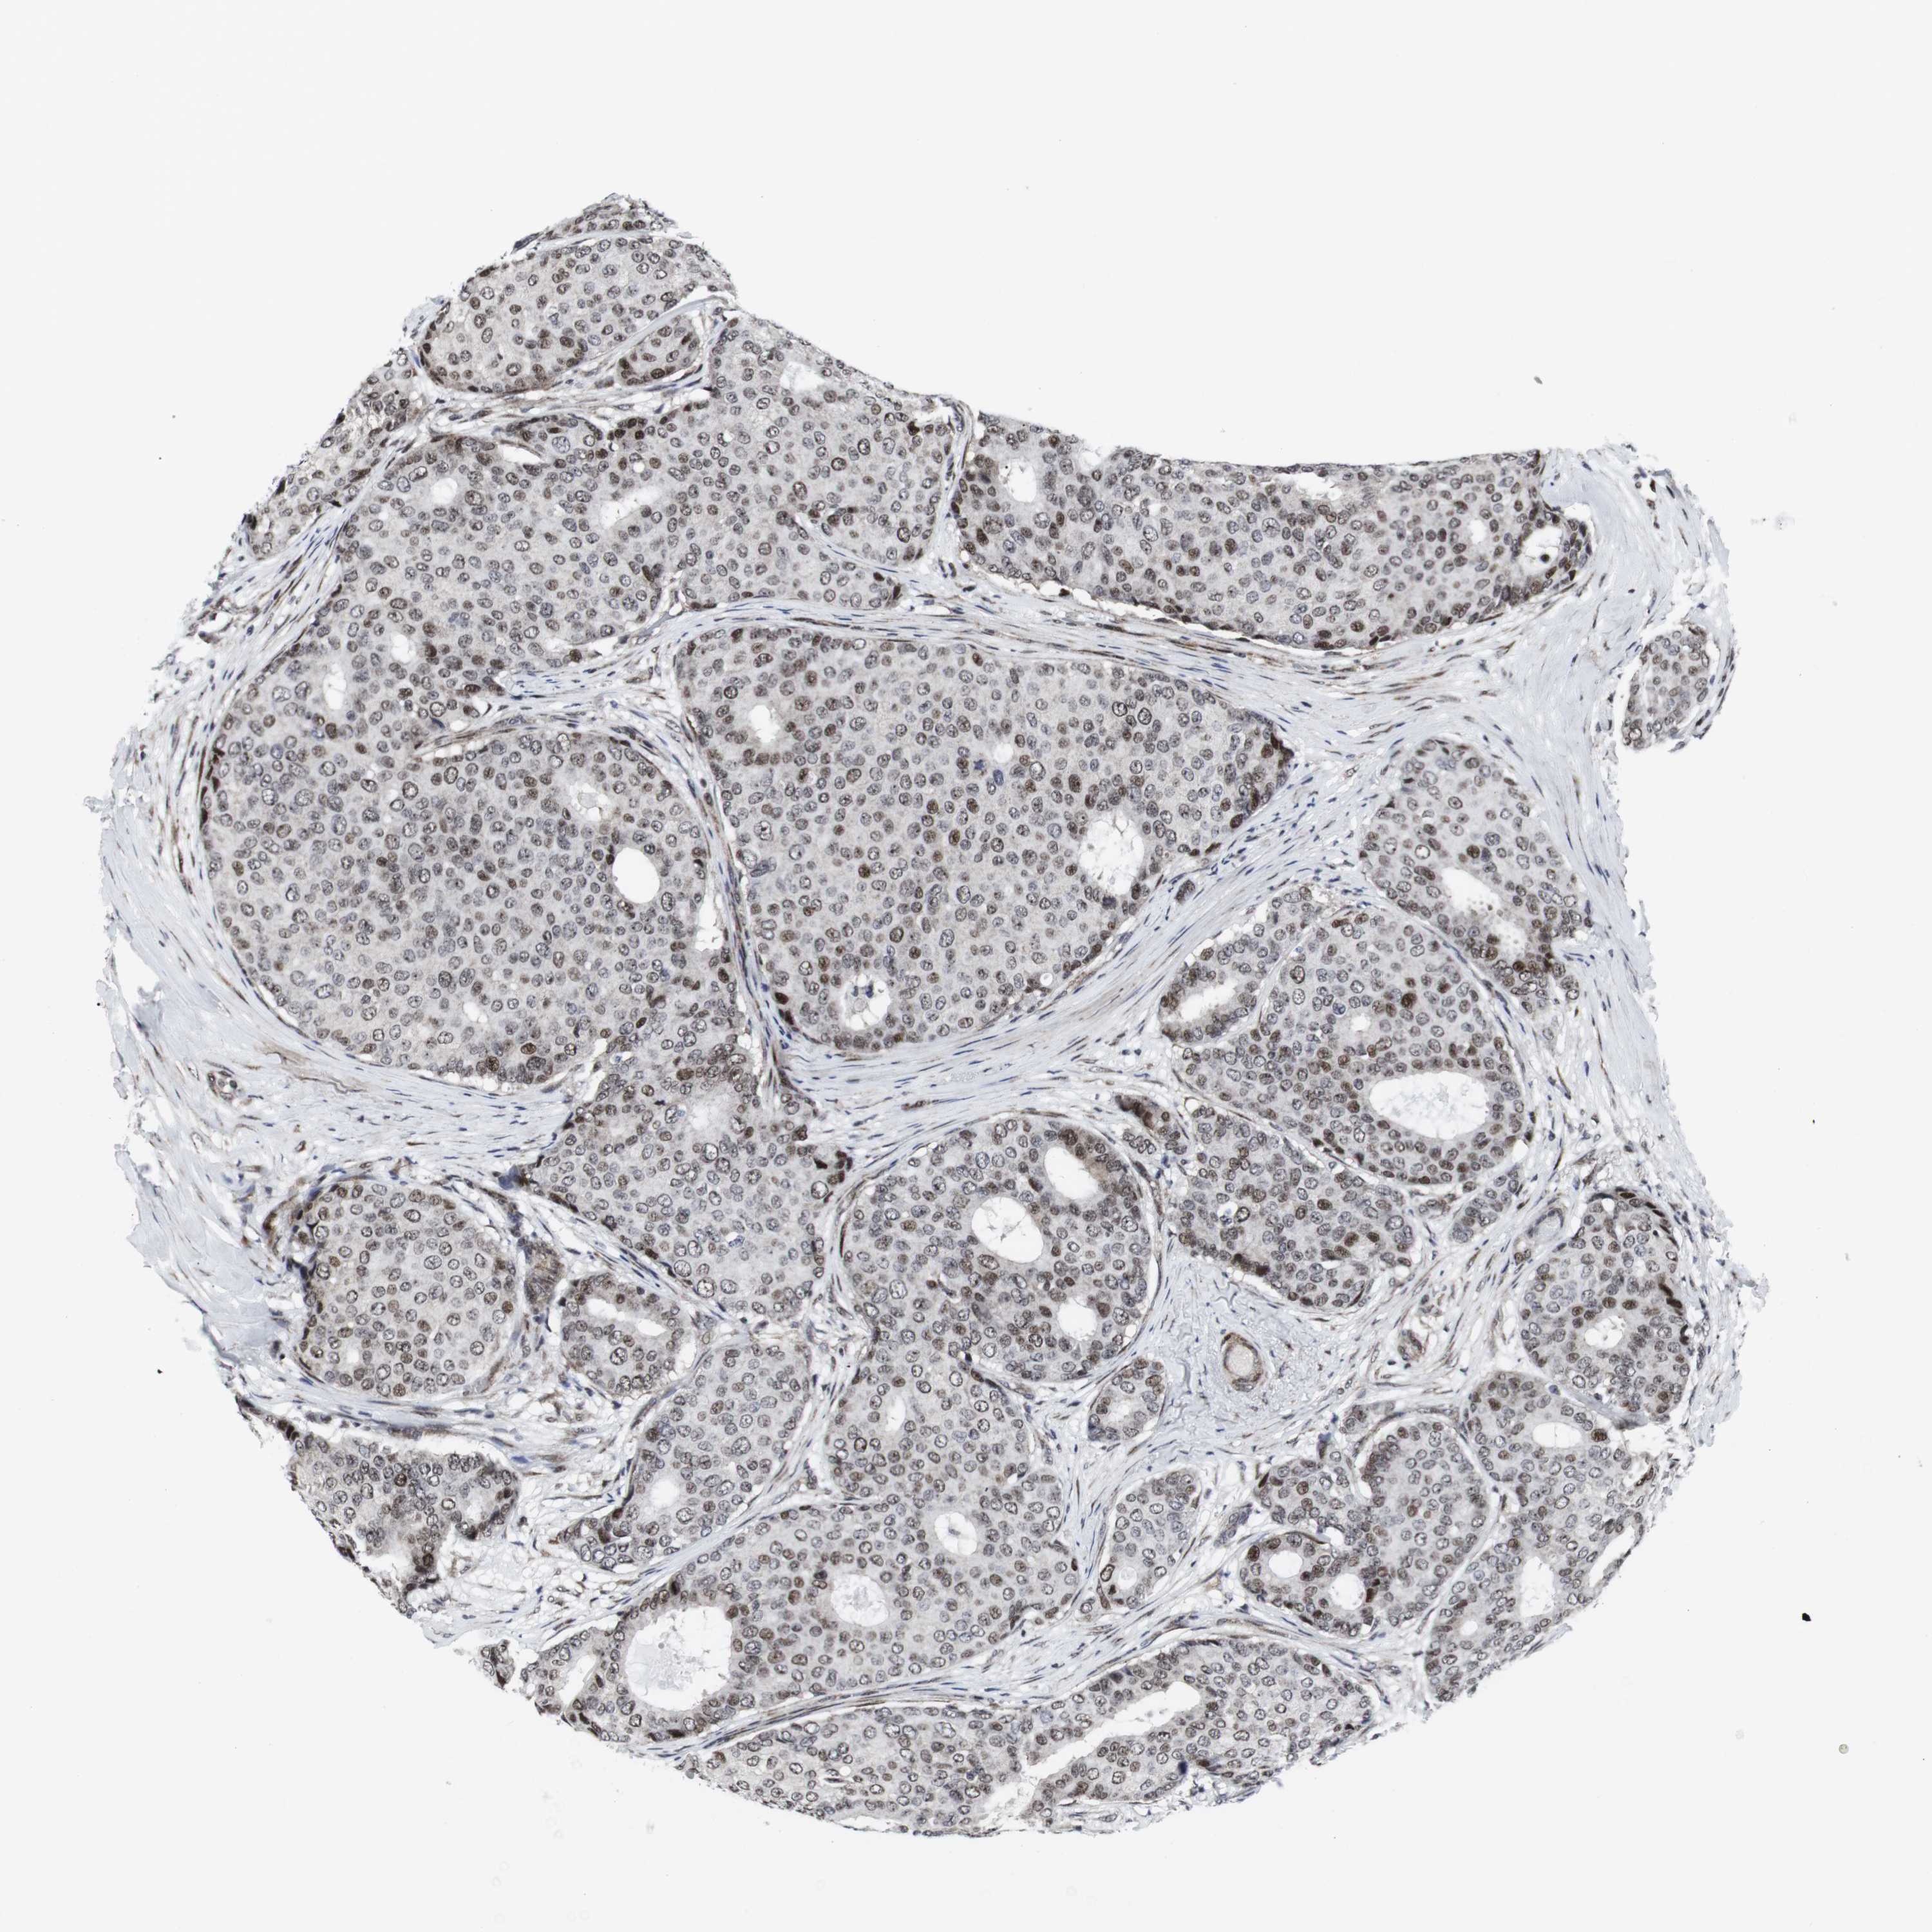

CANCER BREAST CANCER Show tissue menu

BRCA TCGA BRCA VALIDATION PROTEIN EXPRESSION